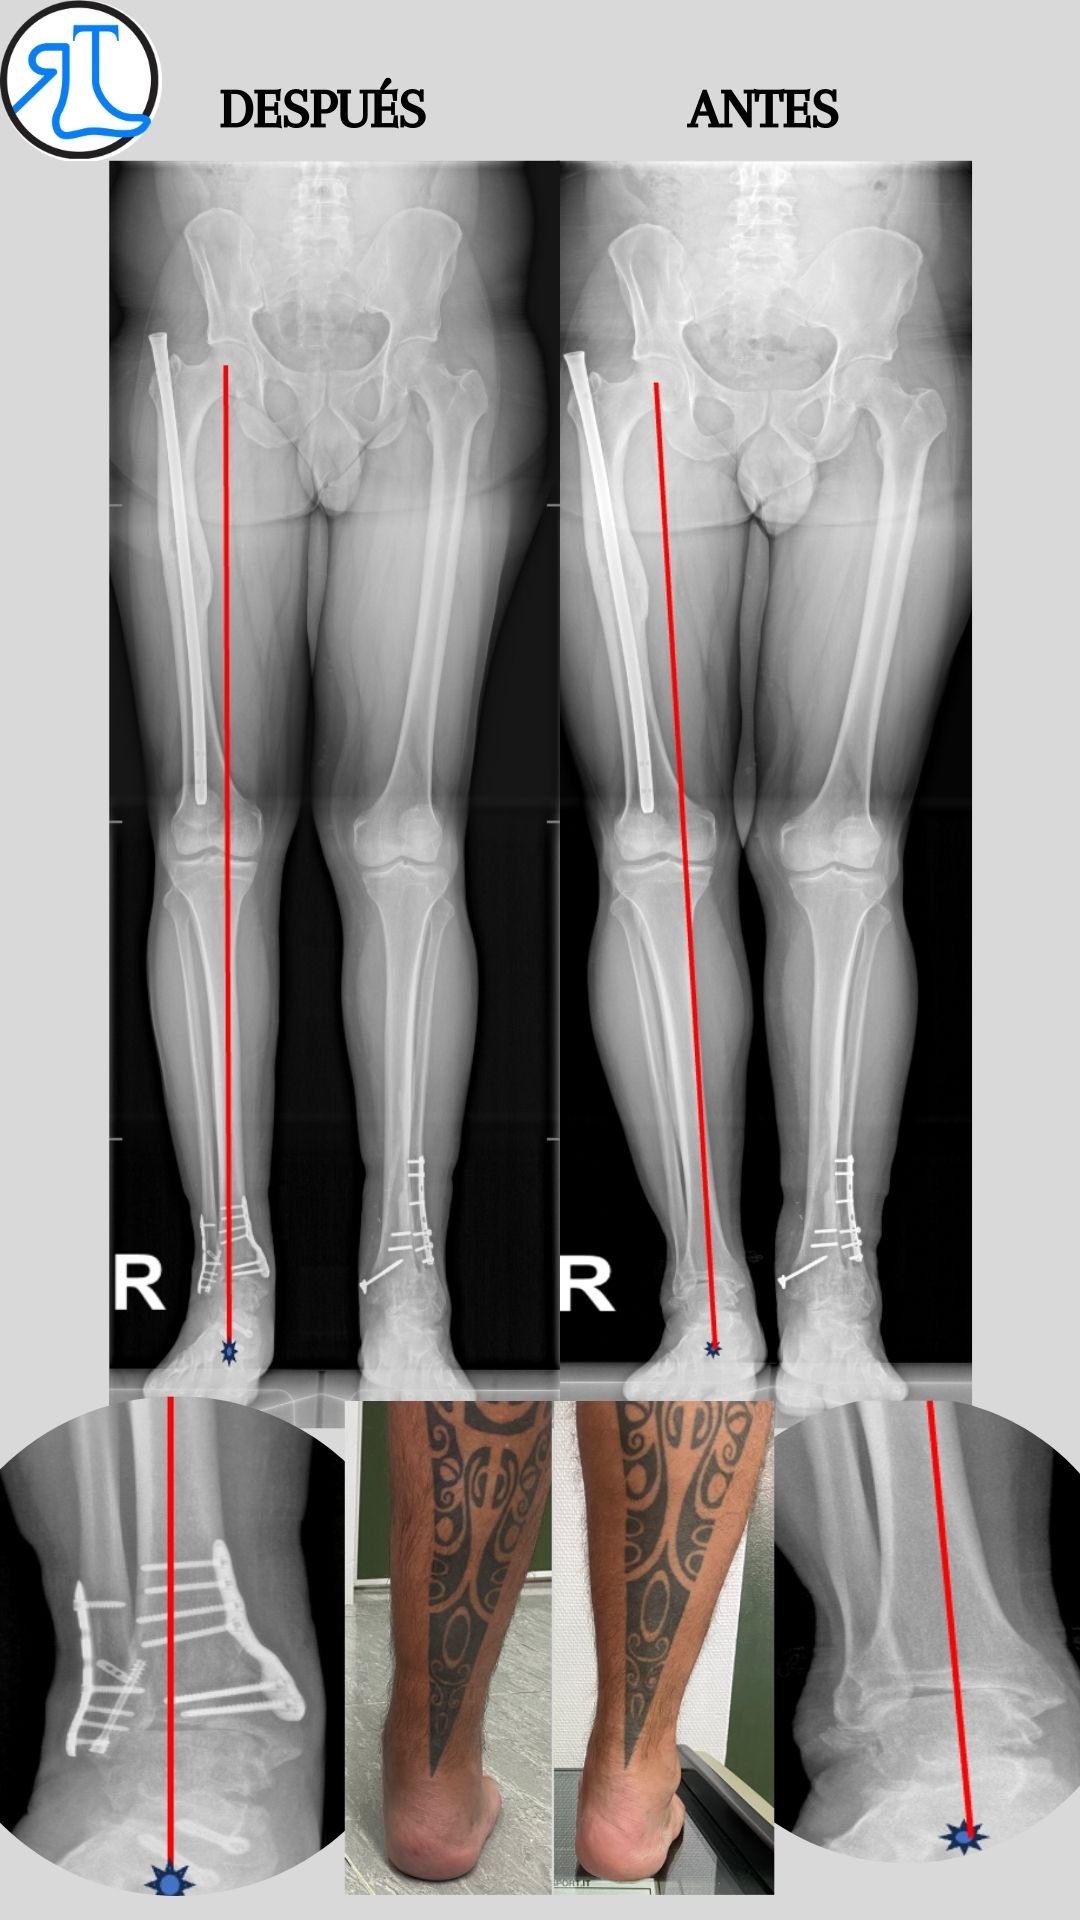

Se objetiva mediante las pruebas de imagen una artrosis asimétrica de tobillo en varo con una inclinación talar (tilt talar) de 9º correspondiente a un grado IIIB de Takakura.

Como podéis ver en las imágenes se consiguió mejorar el eje del talón trasladando el eje de carga de al extremidad hacia la zona del tobillo más sana. A pesar de no corregir del todo el tilt talar el paciente se encuentra asintomático.